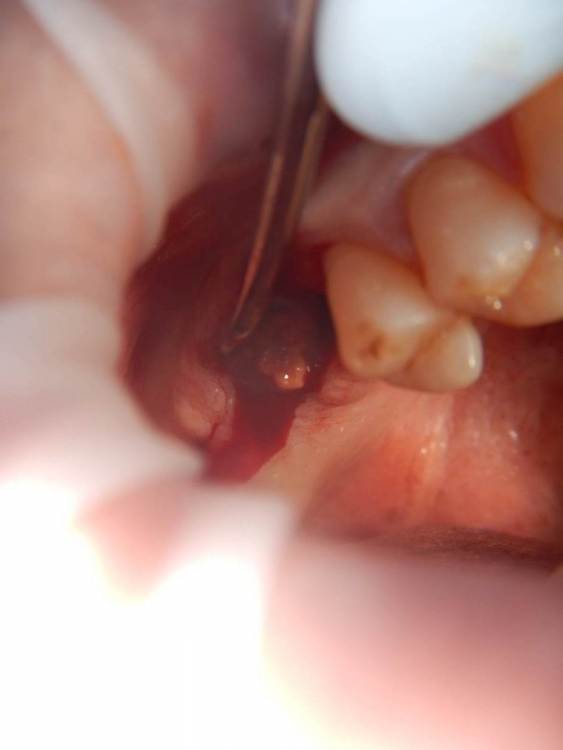

annda Опубликовано 11 июня, 2021 Поделиться Опубликовано 11 июня, 2021 (изменено) Ничего не беспокоит.Зубы удалены лет 15 назад Изменено 11 июня, 2021 пользователем annda 1 Ссылка на комментарий

dentikl Опубликовано 11 июня, 2021 Поделиться Опубликовано 11 июня, 2021 может кто кость выращивал и оно осталось? Ссылка на комментарий

Astronaft Опубликовано 11 июня, 2021 Поделиться Опубликовано 11 июня, 2021 Радиография была один в один с вашим случаем. Результат биопсии: рецидуальная киста с кристаллами холестерина. Но конечно может быть что-нибудь другое. 4 Ссылка на комментарий

Astronaft Опубликовано 12 июня, 2021 Поделиться Опубликовано 12 июня, 2021 (изменено) В моем случае процесс одонтогенный. Киста это остаток после удаления зуба. В вашем случае не должен быть из пазухи. Да - там есть истончение кортикальной пластины в одном месте, но вроде как без инвагинации. Границы везде четкие, т.е. процесс доброкачественный. Из пазухи в кость можно проникнуть только инвазивно. Лизис, а не раздвигание. Карцинома - границы были бы другие. Т.е. процесс либо происходит из самой кости, или одонтогенный. Изменено 12 июня, 2021 пользователем Astronaft 1 Ссылка на комментарий